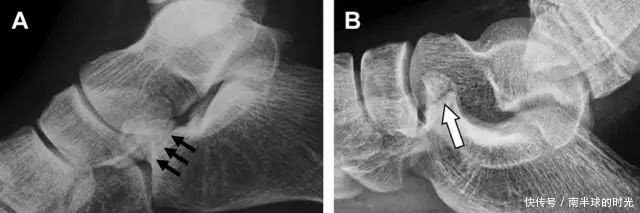

距骨后突骨折

距骨后突有内侧结节和外侧结节,距骨后突内侧结节撕脱性骨折常发生在背屈内旋的暴力作用下。严重跖屈时,胫骨后缘和跟骨挤压距骨后突外侧结节呈楔形,易发生粉碎性骨折。这些骨折细微且需与三角骨鉴别。侧位片观察距骨后突骨折最佳,常规拍片很难发现,当高度怀疑这种骨折又没法做 CT 时,建议加做多个角度的外旋斜位片(图 5)。

图 5 距骨后突骨折。侧位片(A)和 MRI 矢状位 T1 加权像(B)均示后外侧突的简单骨折(箭头),再次阅片时才发现 X 线片上的骨折;侧位片(C)和 CT 横断面图像示后内侧突的粉碎型骨折(箭头)